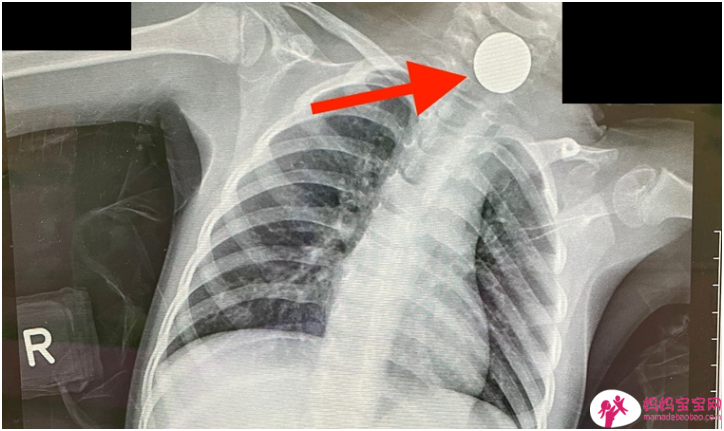

家中准备好防撞地垫、安全围栏,爸妈们杜绝了一切可能伤害宝宝的风险,但家中还隐藏了另一重危机。玩具巴克球、电池、硬币、磁铁、干燥剂等一切日常小物品都有可能被好奇心重...